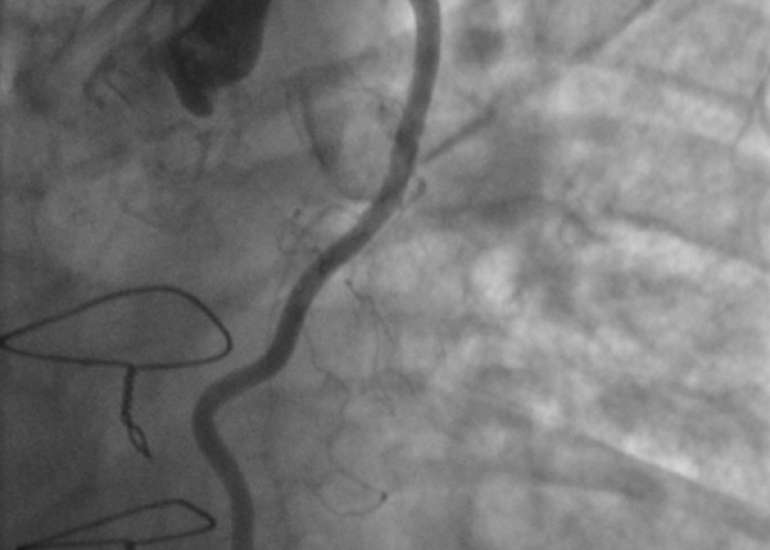

Dr. Yadava completed his medical graduation and Masters in Surgery from Maulana Azad Medical College and had joined Armed Forces as a Surgical Specialist. He cleared his DNB Examination in General Surgery in the year 1983 and completed his training in cardiothoracic surgery at the Cardio Thoracic Center, Armed Forces Medical College, Pune in 1985. For advanced training, went to Australia and worked under and along with some of the greatest cardiac surgeons of recent times. Besides adult cardiac surgery, he was also trained in Paediatric Cardiac Surgery in Melbourne & Japan and successfully cleared the National Boards in Cardiothoracic Surgery (DNBE). He was honoured with Membership of the National Academy of Medical Sciences (MNAMS) in 1994; FICC in 2003, FIACS in 2005 & FCSI in 2012. He has as an experience of over 12,000 open heart surgical procedures and his special field of interest is coronary artery bypass surgery especially total arterial revascularisation & beating heart surgeries (Minimally Invasive).